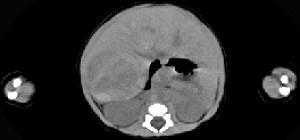

男,5天,上腹部膨隆,CT所见如图,最可能的诊断是 ( )A、肝脓肿B、肝转移瘤C、肝母细胞瘤D、肝血管瘤E、原发性肝癌

问题 男,5天,上腹部膨隆,CT所见如图,最可能的诊断是 ( )

选项 A、肝脓肿 B、肝转移瘤 C、肝母细胞瘤 D、肝血管瘤 E、原发性肝癌

答案 C